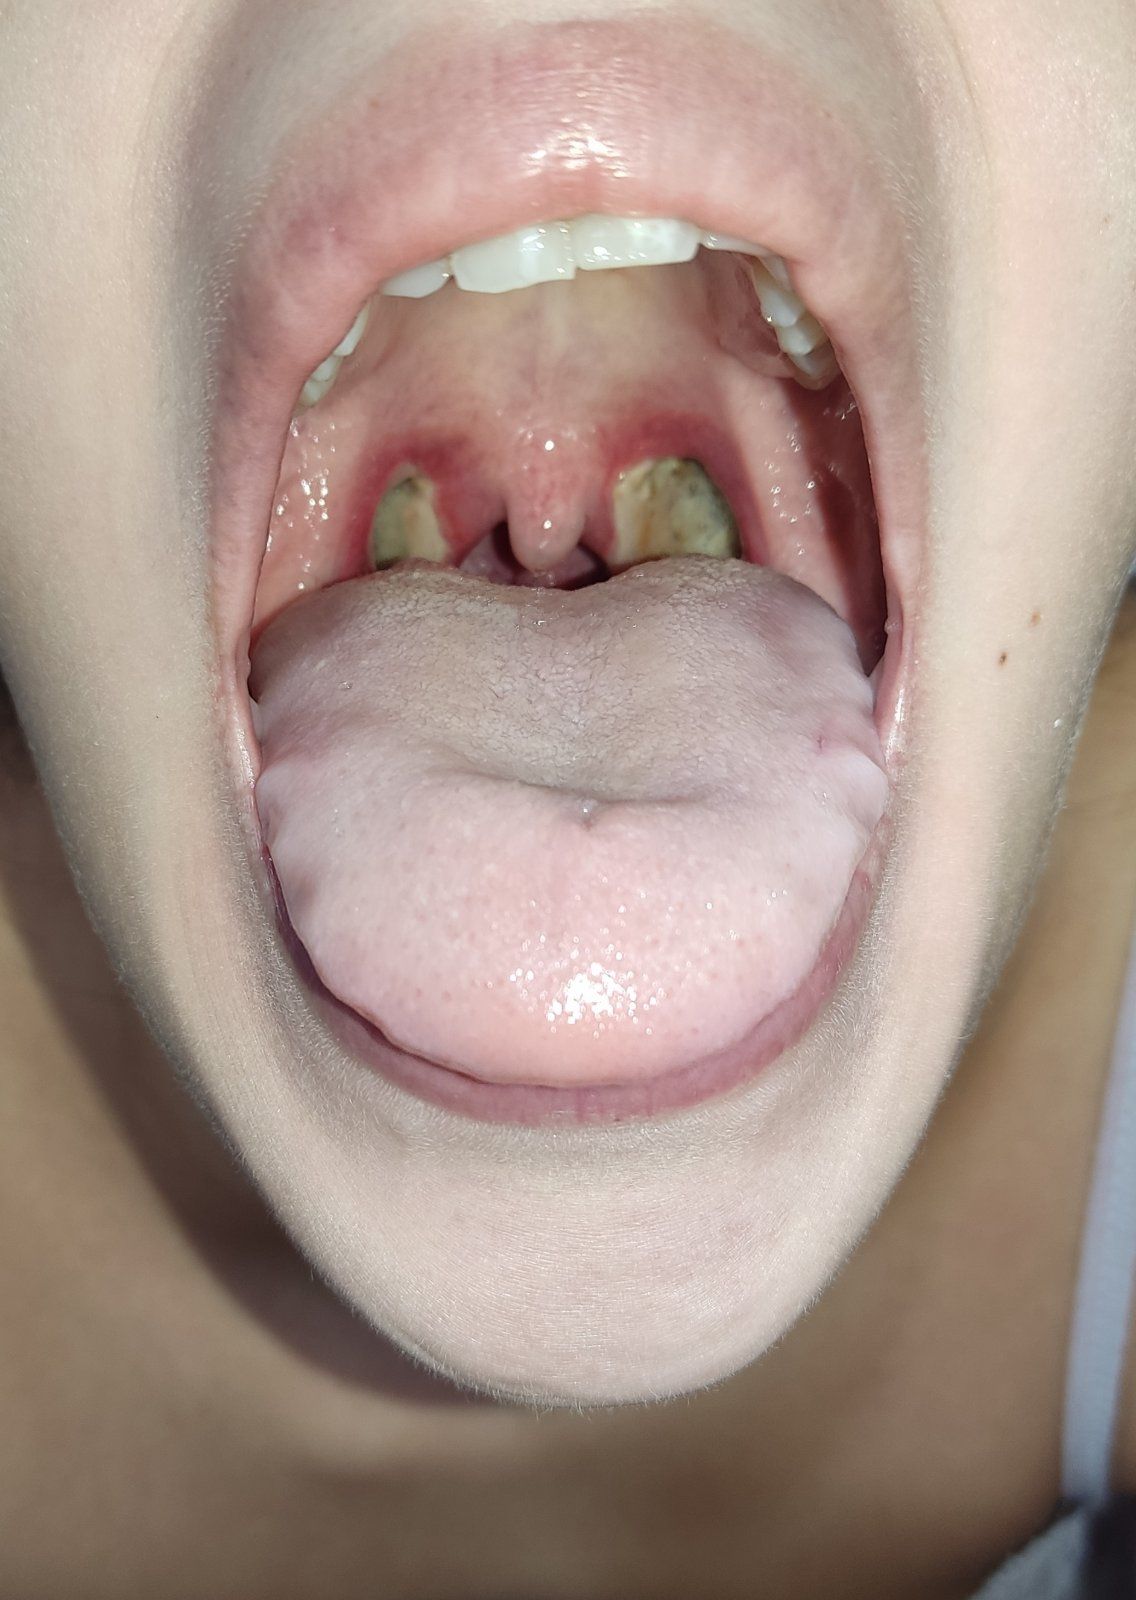

Αμυγδαλεκτομή είναι η χειρουργική πράξη κατά την οποία αφαιρούνται οι αμυγδαλές. Οι αμυγδαλές είναι μέρος του ανοσοποιητικού μας συστήματος (άμυνα του οργανισμού) και βρίσκονται τοποθετημένες δεξιά και αριστερά στο εσωτερικό μέρος του λαιμού μπροστά από το φάρυγγα.

- Αμυγδαλόλιθοι. Χαρακτηριστικά στερεά και σκληρά ξένα σώματα τα οποία παράγονται από τις αμυγδαλές. Τις περισσότερες φορές αποβάλλονται μόνα τους. Όμως δημιουργούν τοπική φλεγμονή πόνο και πολλές φορές αιμορραγία.